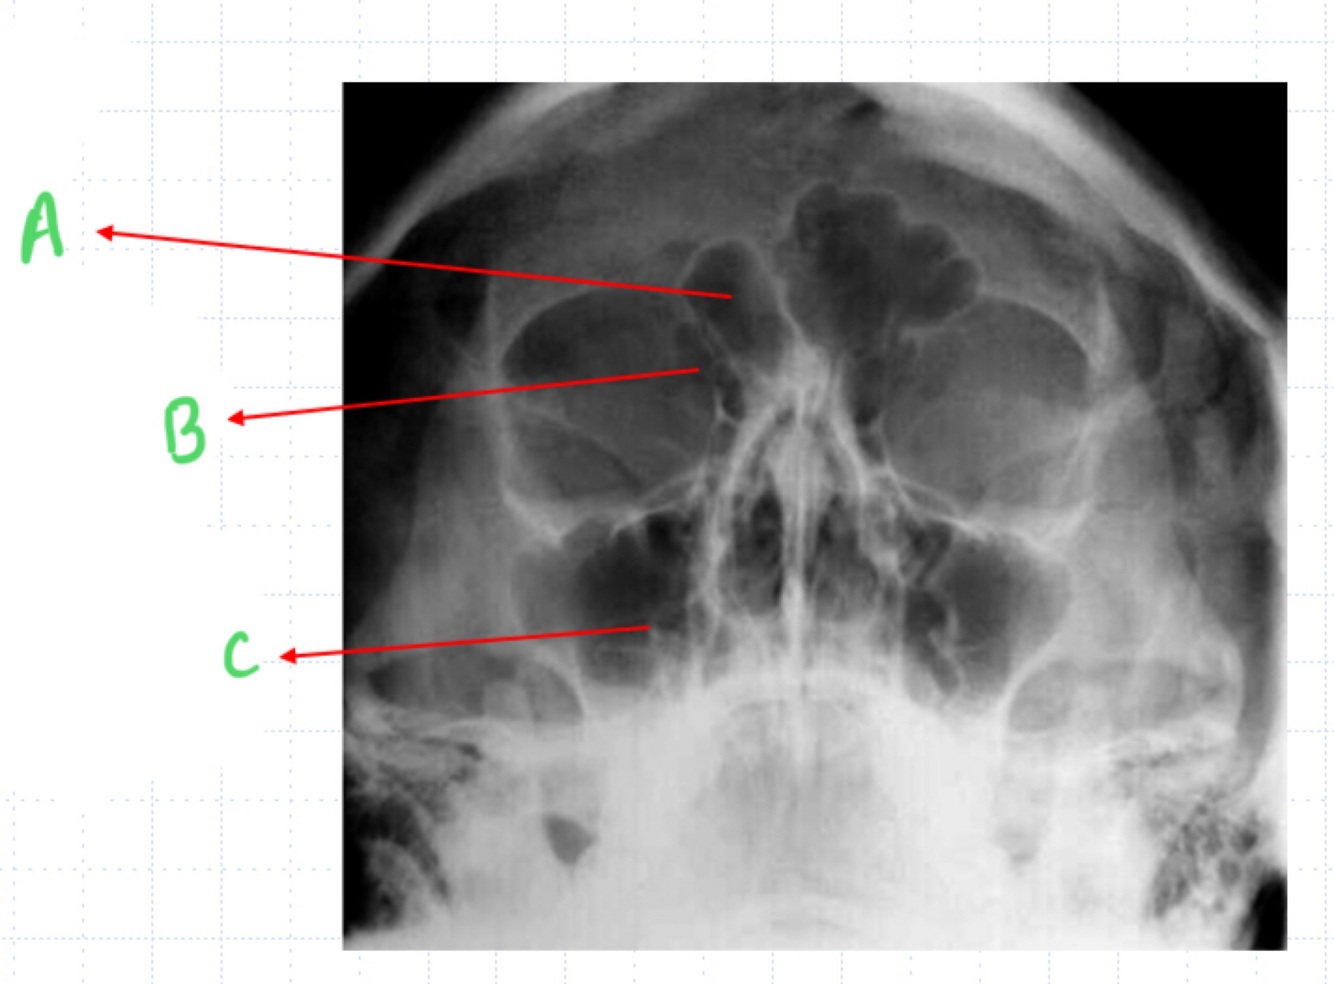

Name the sinuses in the x-ray

A = frontal

B = ethmoid air cells

C = maxillary sinus